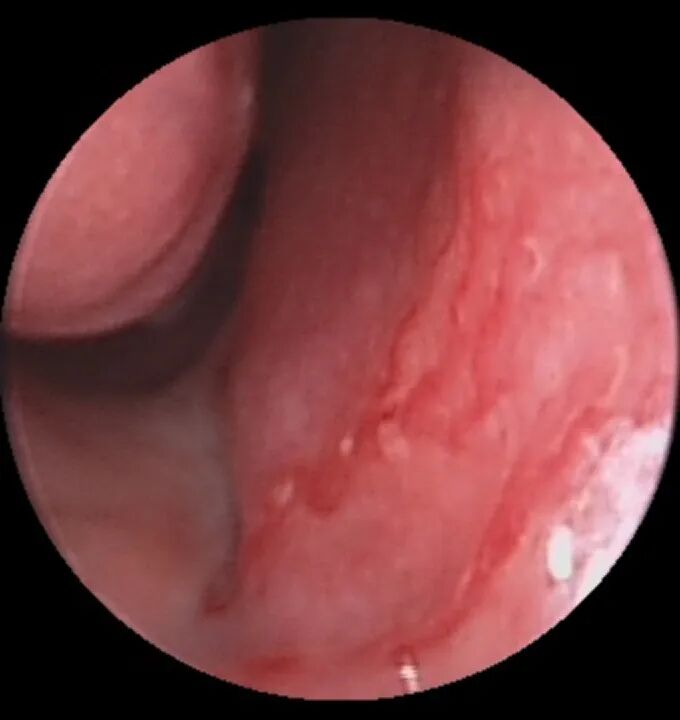

1. 首先,需要在鼻内镜下寻找出血点,这个在门诊进行即可。如下图可以看到鼻腔出血的部位,粘膜表面有小血管喷出血液,这便是明确的出血部位。

图:右鼻黎氏区见小动脉断端喷射出血